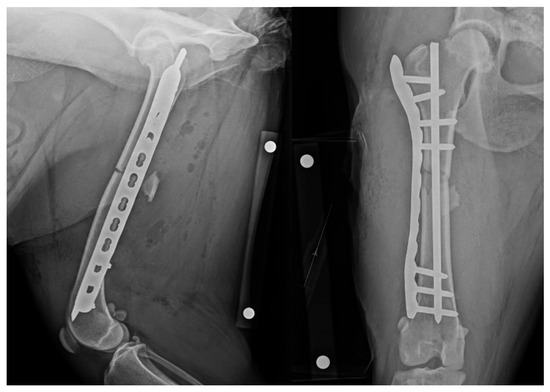

2.5. Revision

The patient was returned to theatre and prepared in a similar manner. The IMP was removed and replaced with a new pin of equal diameter. Insertion position was gauged using tactile feedback of the distal pin engaging the distal metaphysis. Repeated radiographic projections showed appropriate IMP placement (Figure 2). The final fixation construct was assessed as appropriate and satisfied the minimum recommendation for bridging fixation using a locking compression plate, i.e., ≥2 screws or ≥4 cortices in each fragment [19]. Total surgery time, including revision, was 105 min.

Figure 2. Revision post-operative mediolateral and craniocaudal radiographic projections with revised appropriate intramedullary pin length. NB a calibration marker is present, with a distance of 10 cm between the centre of the metal spheres.